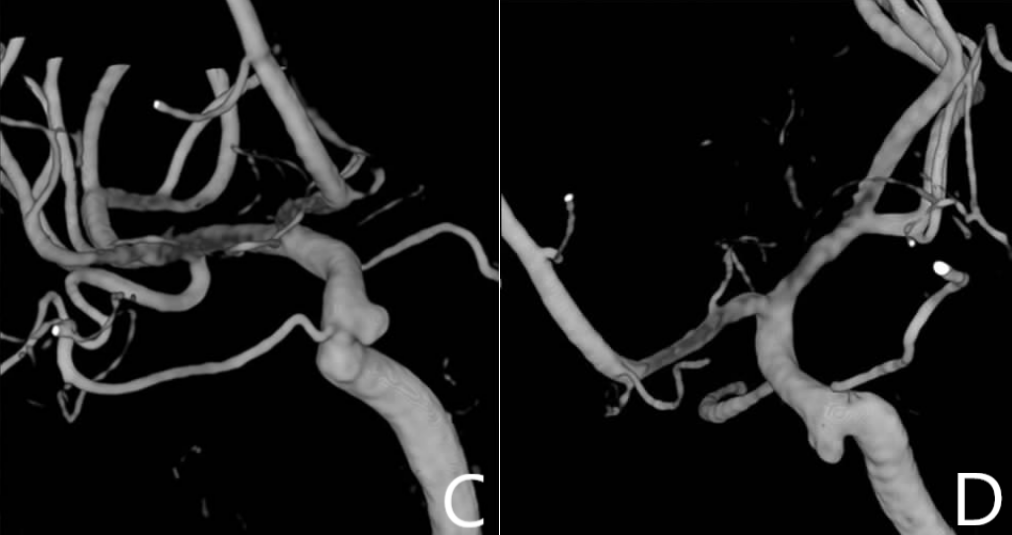

根据患者病史、查体及辅助检查结果,入院诊断考虑垂体腺瘤术后复发,右侧颈内动脉眼动脉段动脉瘤。进一步行DSA脑血管造影检查,结果显示为双侧颈内动脉眼动脉段动脉瘤(图2)。

图2. 脑血管造影提示双侧颈内动脉眼动脉段动脉瘤。